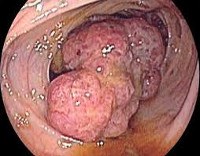

Следующий этап исследования - проведение колоноскопии, которая позволяет выявить небольшие по размеру опухоли толстого кишечника, осмотреть его на всем протяжении. Также с помощью этого метода можно взять биоптат и удалить небольшого размера полипы. Колоноскопия имеет большую чувствительность по сравнению с ирригоскопией, но наиболее достоверные результаты можно получить при использовании эндоскопии и контрастной рентгенографии.